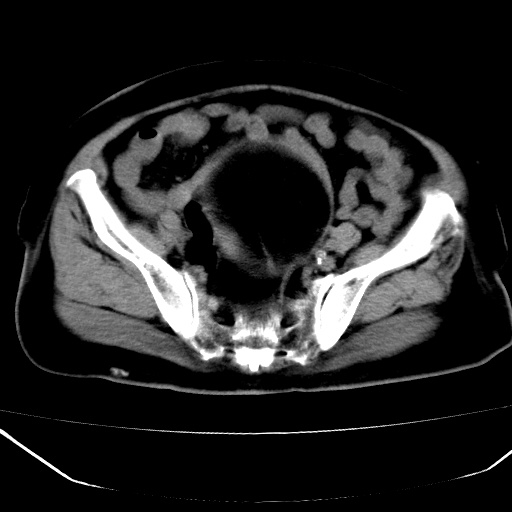

患者,女,74岁,无不适,b超示盆腔包块。

子宫前上方巨大脂性肿物,肿物边缘为较厚软组织密度影,其内缘欠光整,脂性密度中央见结节状软组织密度影“漂浮”,肿物与子宫前壁关系密切,考虑1脂肪瘤2皮样囊肿3肌瘤脂样变

ct值-90hu